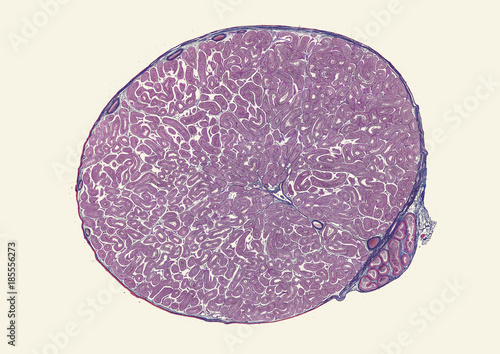

Mikrofotografi - Plakater, Poster, Billeder på lærred